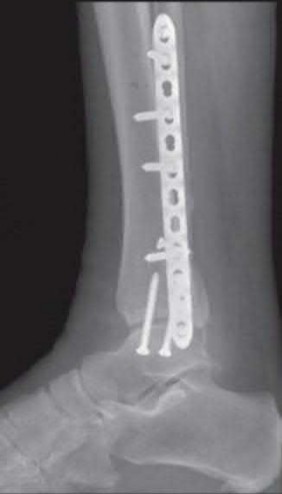

The patient presents with a closed distal third metaphyseal-diaphyseal distal tibia fracture with simple intra-articular extension. Immediate intramedullary nailing along with percutaneous fixation of the articular component provides appropriate restoration of length, rotation and alignment and minimizes the risk of wound complication.

Displaced distal third tibia fractures may be associated with simple intraarticular extension. Operative treatment of intra-articular distal tibia fractures has historically been performed with open reduction and internal fixation. Early open reduction and plate fixation of pilon fractures has been associated with high rates of infection and wound complication. In select patterns with simple articular extension, percutaneous screw fixation and medullary nailing may provide appropriate reduction with minimal soft-tissue risk.

Marcus et al. evaluated the outcomes of immediate intramedullary nailing and percutaneous fixation of simple intra-articular distal tibia fractures (AO/OTA 43 C1 and C2). The authors found excellent rates of union and alignment, however caution against broad application of this technique until more rigorous randomized studies can be performed.

Sirkin et al. retrospectively evaluated the results of a staged approach to management of intra-articular distal tibia fractures with temporary bridging external fixation followed by open reduction and internal fixation (ORIF). The authors found decreased rates of wound complication and infection compared with prior studies.

Figures A and B demonstrate a distal third tibial shaft fracture with simple intra-articular extension. The axial and coronal CT cuts in Figures C and D further clarify the articular injury. Illustrations A and B demonstrate a comminuted distal third tibial fracture with simple intra-articular extension. Illustrations C and D are fluoroscopic images of the same injury after intramedullary nailing and percutaneous fixation of the articular component.

A 25-year-old female is involved in a motor vehicle collision. She presents with the isolated injury seen in Figures A through D. Her leg is swollen but her skin is intact. She has no clinical signs of compartment syndrome. Which of the following treatment options will allow for maintenance of fracture alignment and minimize the risk of soft tissue complications?